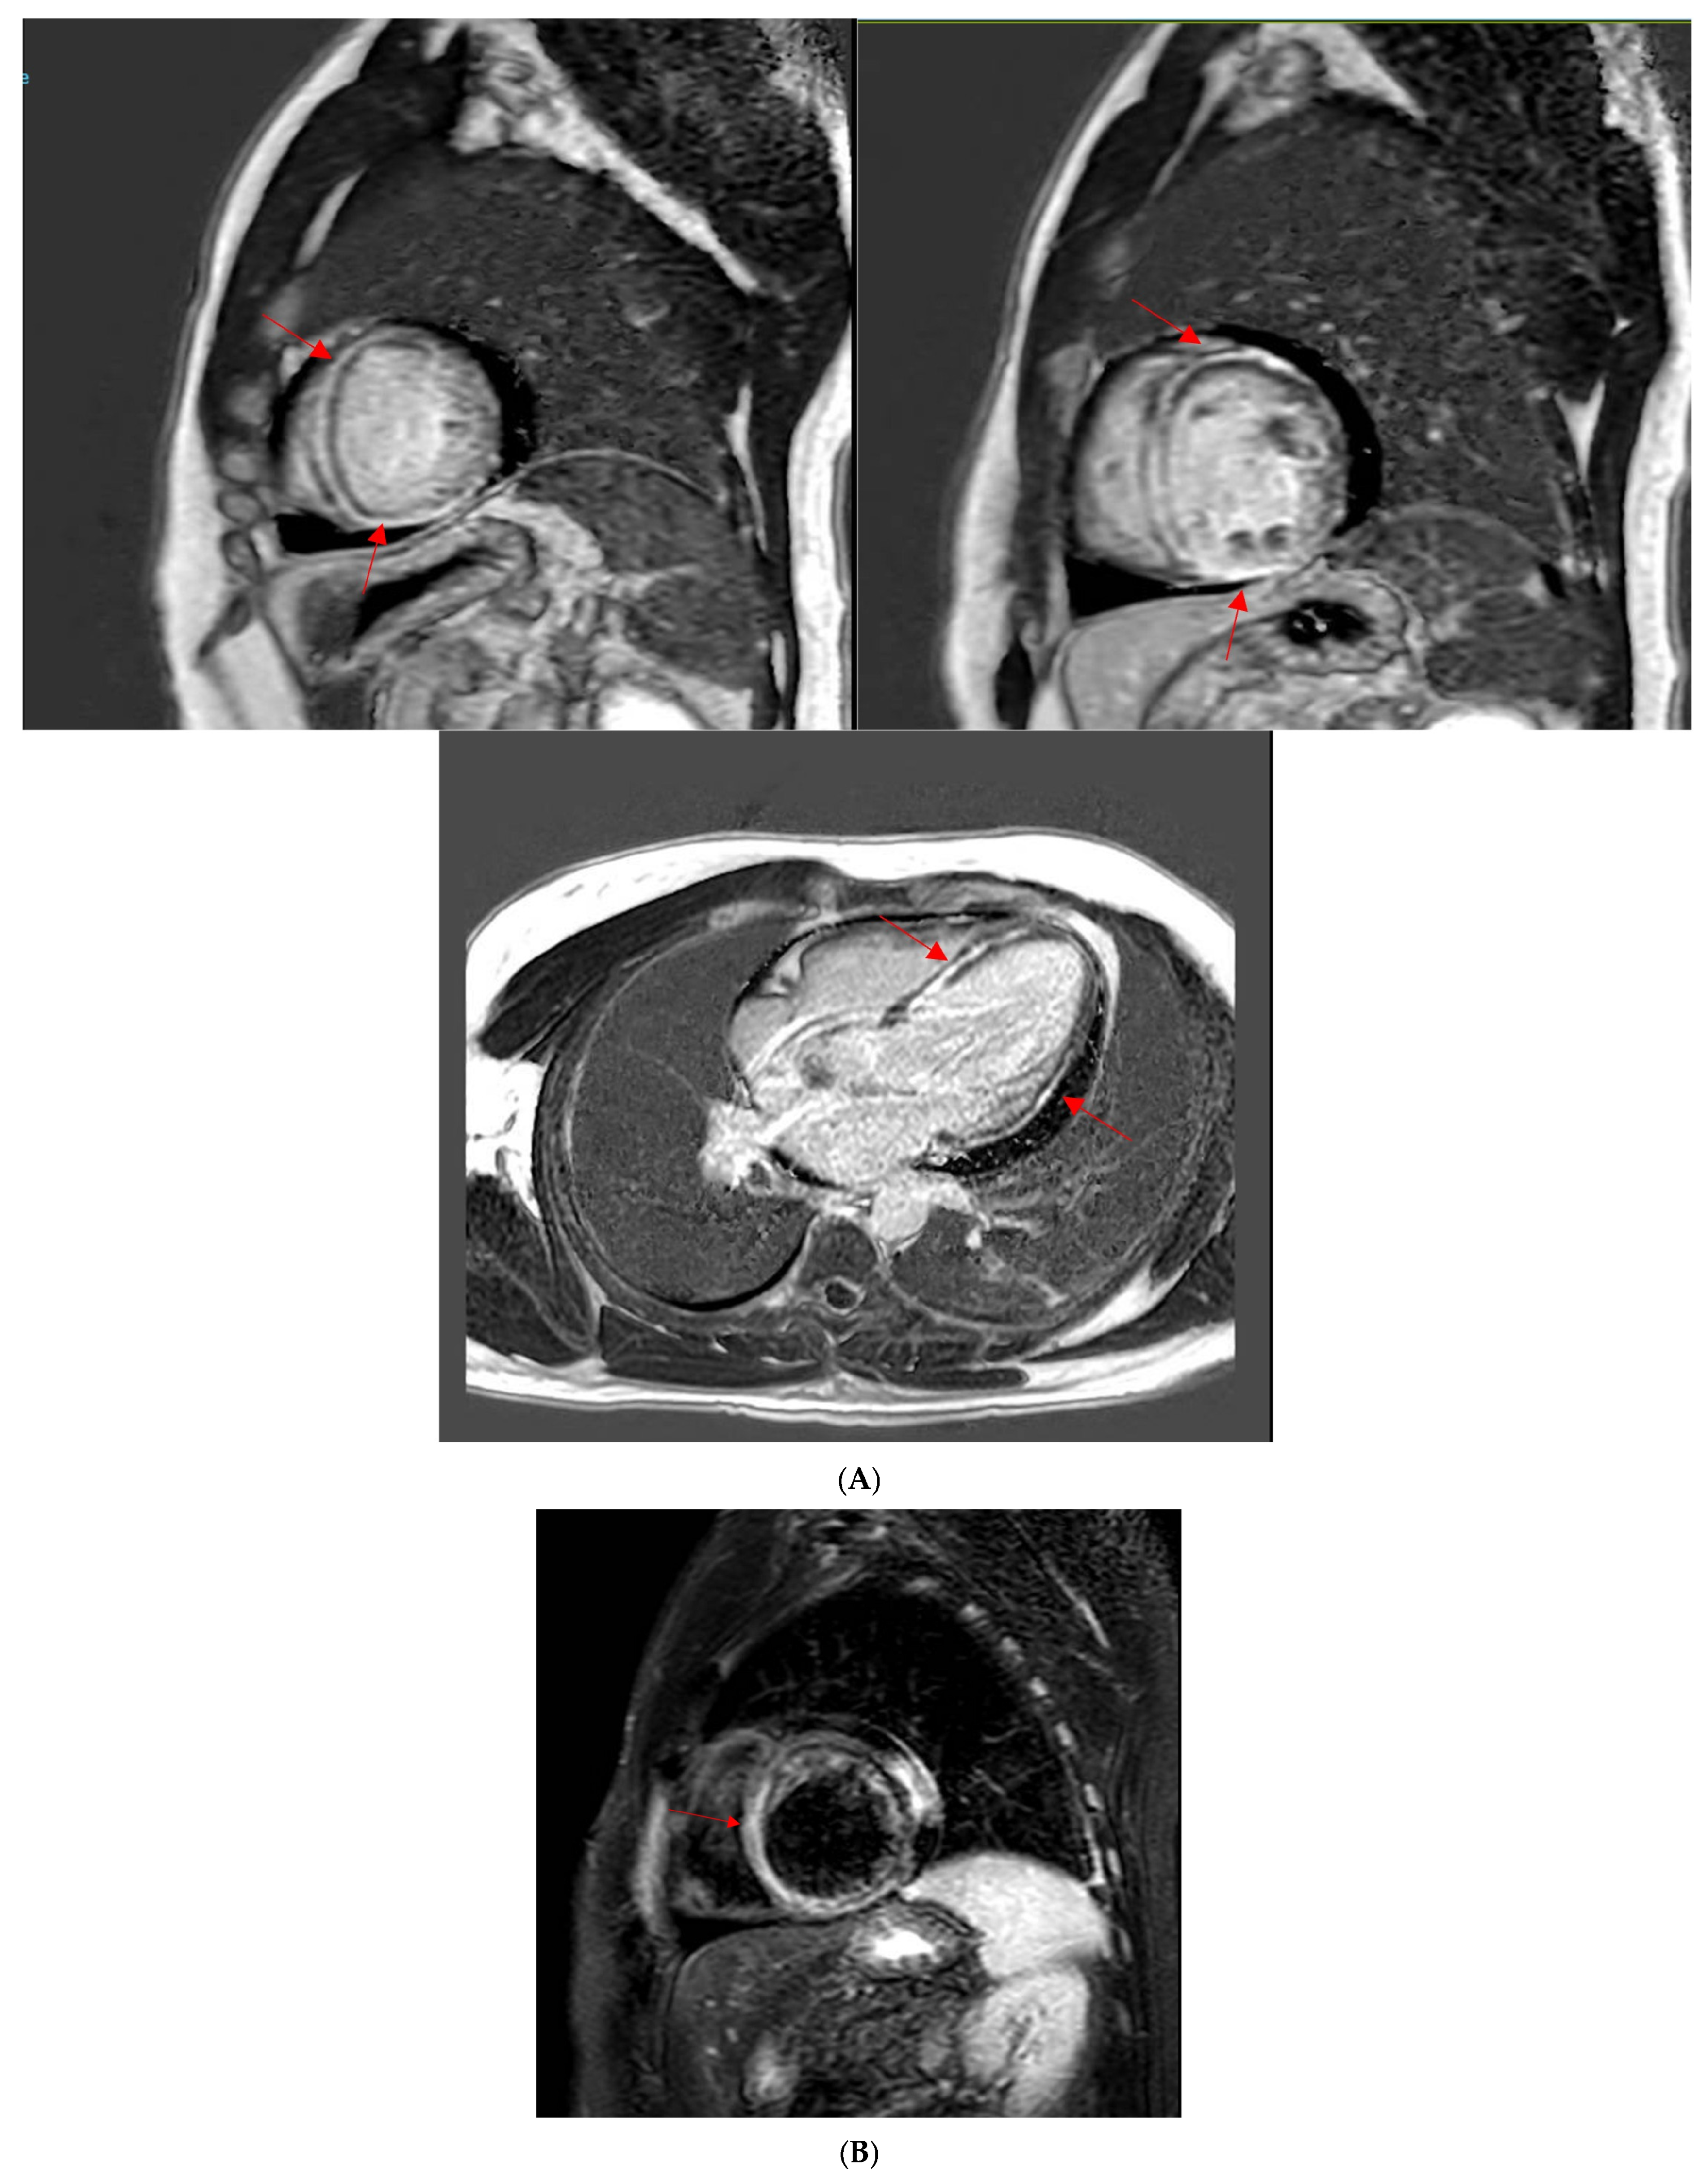

A 49-year-old male patient with a history of human immunodeficiency virus (HIV) was undergoing treatment for Kaposi sarcoma with cabozantinib and nivolumab (ICI) as the third line of treatment. Approximately 2 months after his last treatment, this patient presented to the emergency room with progressive shortness of breath over the last few weeks and was found to be in acute heart failure. An electrocardiogram showed sinus tachycardia with occasional premature ventricular complexes (Figure 2). The troponin I level peaked at 0.62 ng/mL (normal value < 0.03 ng/mL) and the B natriuretic peptide level was 1023 pg/mL (normal value < 100 pg/mL). The baseline echocardiogram prior to treatment initiation showed normal biventricular function, but his echocardiogram at presentation showed severely reduced left ventricular systolic function with an ejection fraction of 30% and a small pericardial effusion (Figure 3). Left heart catheterization demonstrated normal coronary arteries. Right heart catheterization demonstrated minimally elevated filling pressures and borderline cardiac output/index. An endomyocardial biopsy was taken, with pathology showing mild interstitial fibrosis, but no evidence of active myocarditis. Cardiac MRI showed linear mid myocardial LGE in the interventricular septum (Figure 4A) that corresponded with the areas of myocardial edema seen on the T2-weighted images (Figure 4B). There was also elevated native T1 map at 1470 ms (normal 1000 +/− 50 ms at 1.5T) (Figure 4C) along with elevated T2 mapping at 70 ms (myocardial edema suggested if T2 > 55–60 ms) (Figure 4D), and a small pericardial effusion. ECV was unable to be calculated due to an artifact on postcontrast T1 images. This case met the ICOS diagnostic criteria (Table 2, cTn elevation + diagnostic CMR (major criteria)). The patient was started on a pulse dose of corticosteroids for the treatment of presumed myocarditis with significant improvement in symptoms and was discharged home with a stable dose of steroids, as well as goal directed medical therapy for heart failure (beta blockers, ARNI, and SGLT2i). Nivolumab was discontinued. The patient was followed-up in the cardio-oncology clinic and, due to the resolution of symptoms, his steroid treatment was tapered over the next few weeks. During his follow-ups, he showed a complete resolution of clinical symptoms and was able to recover a good exercise tolerance, but unfortunately a repeat echocardiogram at 9 months after the initial presentation showed a persistently reduced ejection fraction.

Figure 4. (A) Cardiac MRI LGE images from the clinical patient. Cardiac MRI images showing linear midventricular LGE (red arrows) in the basal and mid interventricular septum, extending into the anterior and inferior LV segments. Globally reduced biventricular function (LVEF 29% and RVEF 42%). (B) Cardiac MRI T2-weighted images from the clinical patient. Cardiac MRI T2-weighted images. There is interventricular T2 enhancement (red arrow) consistent with edema. (C) Cardiac MRI T1 mapping images from the clinical patient. Cardiac MRI T1 mapping images revealed an elevated native T1 map at 1470 ms (normal 1000 +/− 50 ms at 1.5T). (D) Cardiac MRI T2 mapping images from the clinical patient. Cardiac MRI T2 mapping images revealed elevated T2 mapping at 70 ms (myocardial edema suggested if T2 > 55–60 ms).